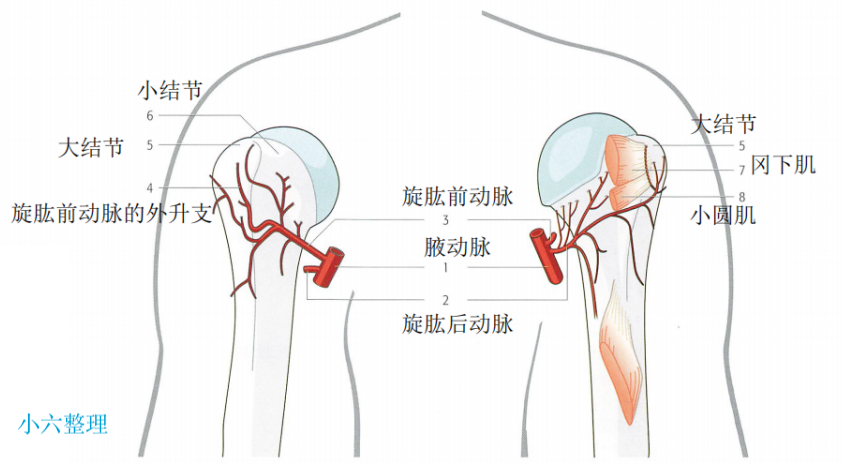

血供